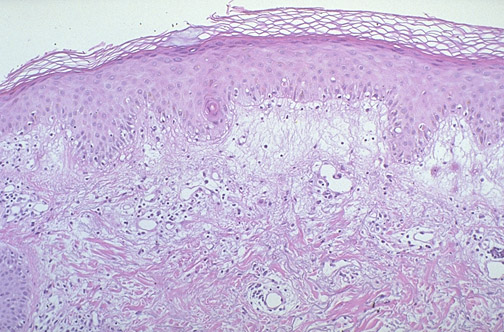

| Here is erythema multiforme. The classic gross "target" lesion on physical examination has a central vesicle surrounded by a zone of erythema. This uncommon, but usually self-limited, disorder may arise as a hypersensitivity reaction to infection, drugs, neoplasia, or collagen vascular diseases. Note the dermal edema with perivascular lymphocytic infiltrates. |